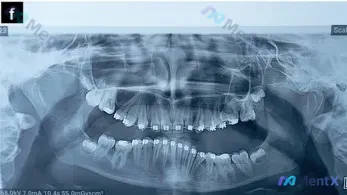

整理了一份13.11岁患者的全景牙齿X光片资料,目前患者处于正畸治疗中,先放核心的影像学发现,大家看看第一眼的评估优先级会怎么排? 已知核心信息: - 恒牙列,全口可见正畸托槽与弓丝 - 双侧上颌第三磨牙已萌出,双侧下颌第三磨牙(38、48)呈近中阻生 - 下颌左侧第一磨牙(36)区域缺失 - 颌骨...